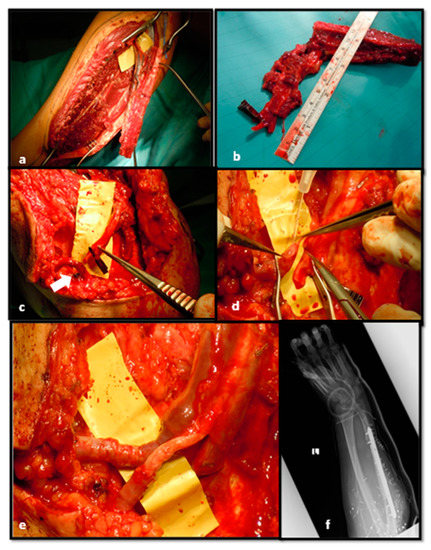

After 14 days, we performed bone reconstruction by contralateral free fibular flap and anastomosed the vessels on AVL, centrally bisected in two parts (Figure 7).

Figure 7. Free flap harvested from contralateral leg (a,b);Fibular pedicle placed near AVL (arrow) (c); AVL bisection at the centre (d); End-to-end fibular peduncle anastomoses on AVL (e); Post-operative x-rays after bone fixation (f).